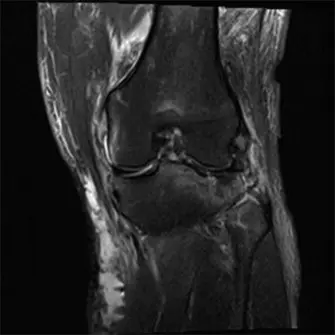

صورة بالأشعة السينية الأولية للركبة اليسرى تُظهر كسرًا مفتتًا ثنائي اللقمة في هضبة الظنبوب مع انخفاض كبير في السطح المفصلي وانفصال بين الجزء المفصلي وجسم العظم، بما يتوافق مع إصابة من النوع السادس حسب تصنيف شاتزكر.

الشكل 1: صورة بالأشعة السينية الأولية للركبة اليسرى تُظهر كسرًا مفتتًا ثنائي اللقمة في هضبة الظنبوب مع انخفاض كبير في السطح المفصلي وانفصال بين الجزء المفصلي وجسم العظم، بما يتوافق مع إصابة من النوع السادس حسب تصنيف شاتزكر.

4. التصوير بالرنين المغناطيسي (MRI):

• عادة ما يُؤجل التصوير بالرنين المغناطيسي في حالات الطوارئ التي تتطلب جراحة فورية لإصلاح الأوعية الدموية أو تثبيت الكسر.

• يُمكن إجراؤه لاحقًا لتقييم الأنسجة الرخوة بشكل أفضل، مثل الغضاريف الهلالية، والأربطة الصليبية والجانبية، التي غالبًا ما تتضرر مع هذه الكسور الشديدة.